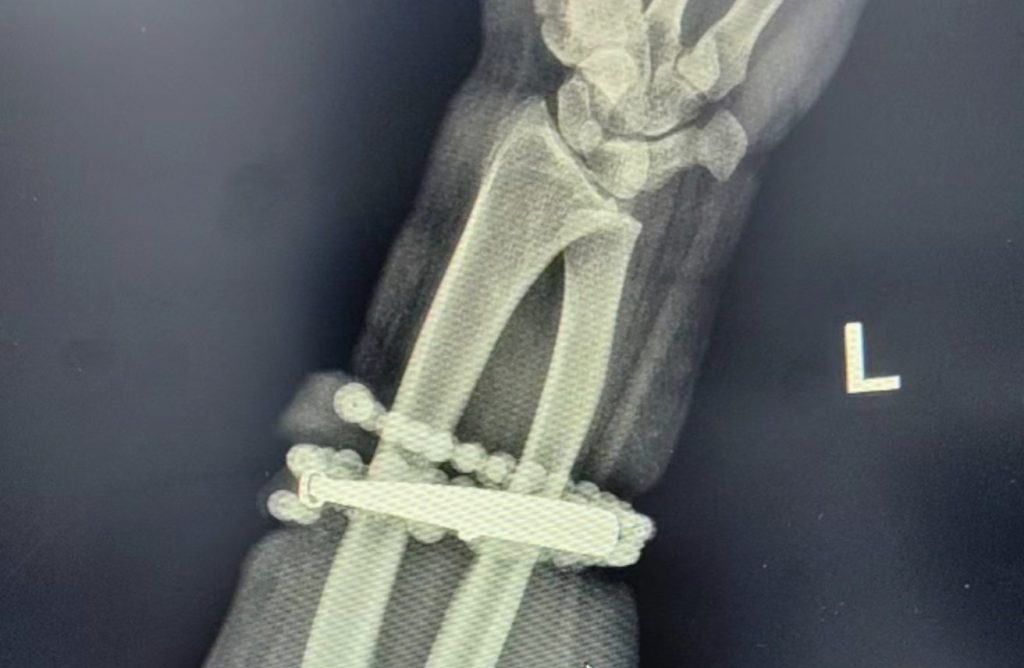

Two weeks ago, her condition worsened, with swelling, severe pain, and pus forming at the site. Upon closer inspection, Gong realized the bangle and beads had partially embedded into her skin and could not be removed, prompting her to seek medical care.

Doctors explained that long-term pressure and friction from the jewelry, combined with bacterial infection, led to chronic inflammation and the growth of granulation tissue. The bracelet had effectively become a foreign object in her body, causing continuous local infection. If left untreated, the infection could have spread and potentially threatened her life or damaged wrist function.

After an hour-long surgical procedure, physicians successfully removed the bracelet and beads, performed debridement, and drained the infected area. Gong’s condition stabilized, and she has since been discharged from the hospital.